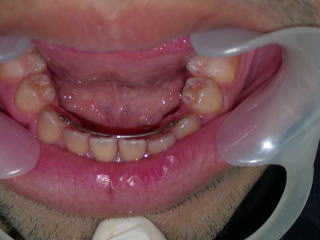

初診平成22年8月28日